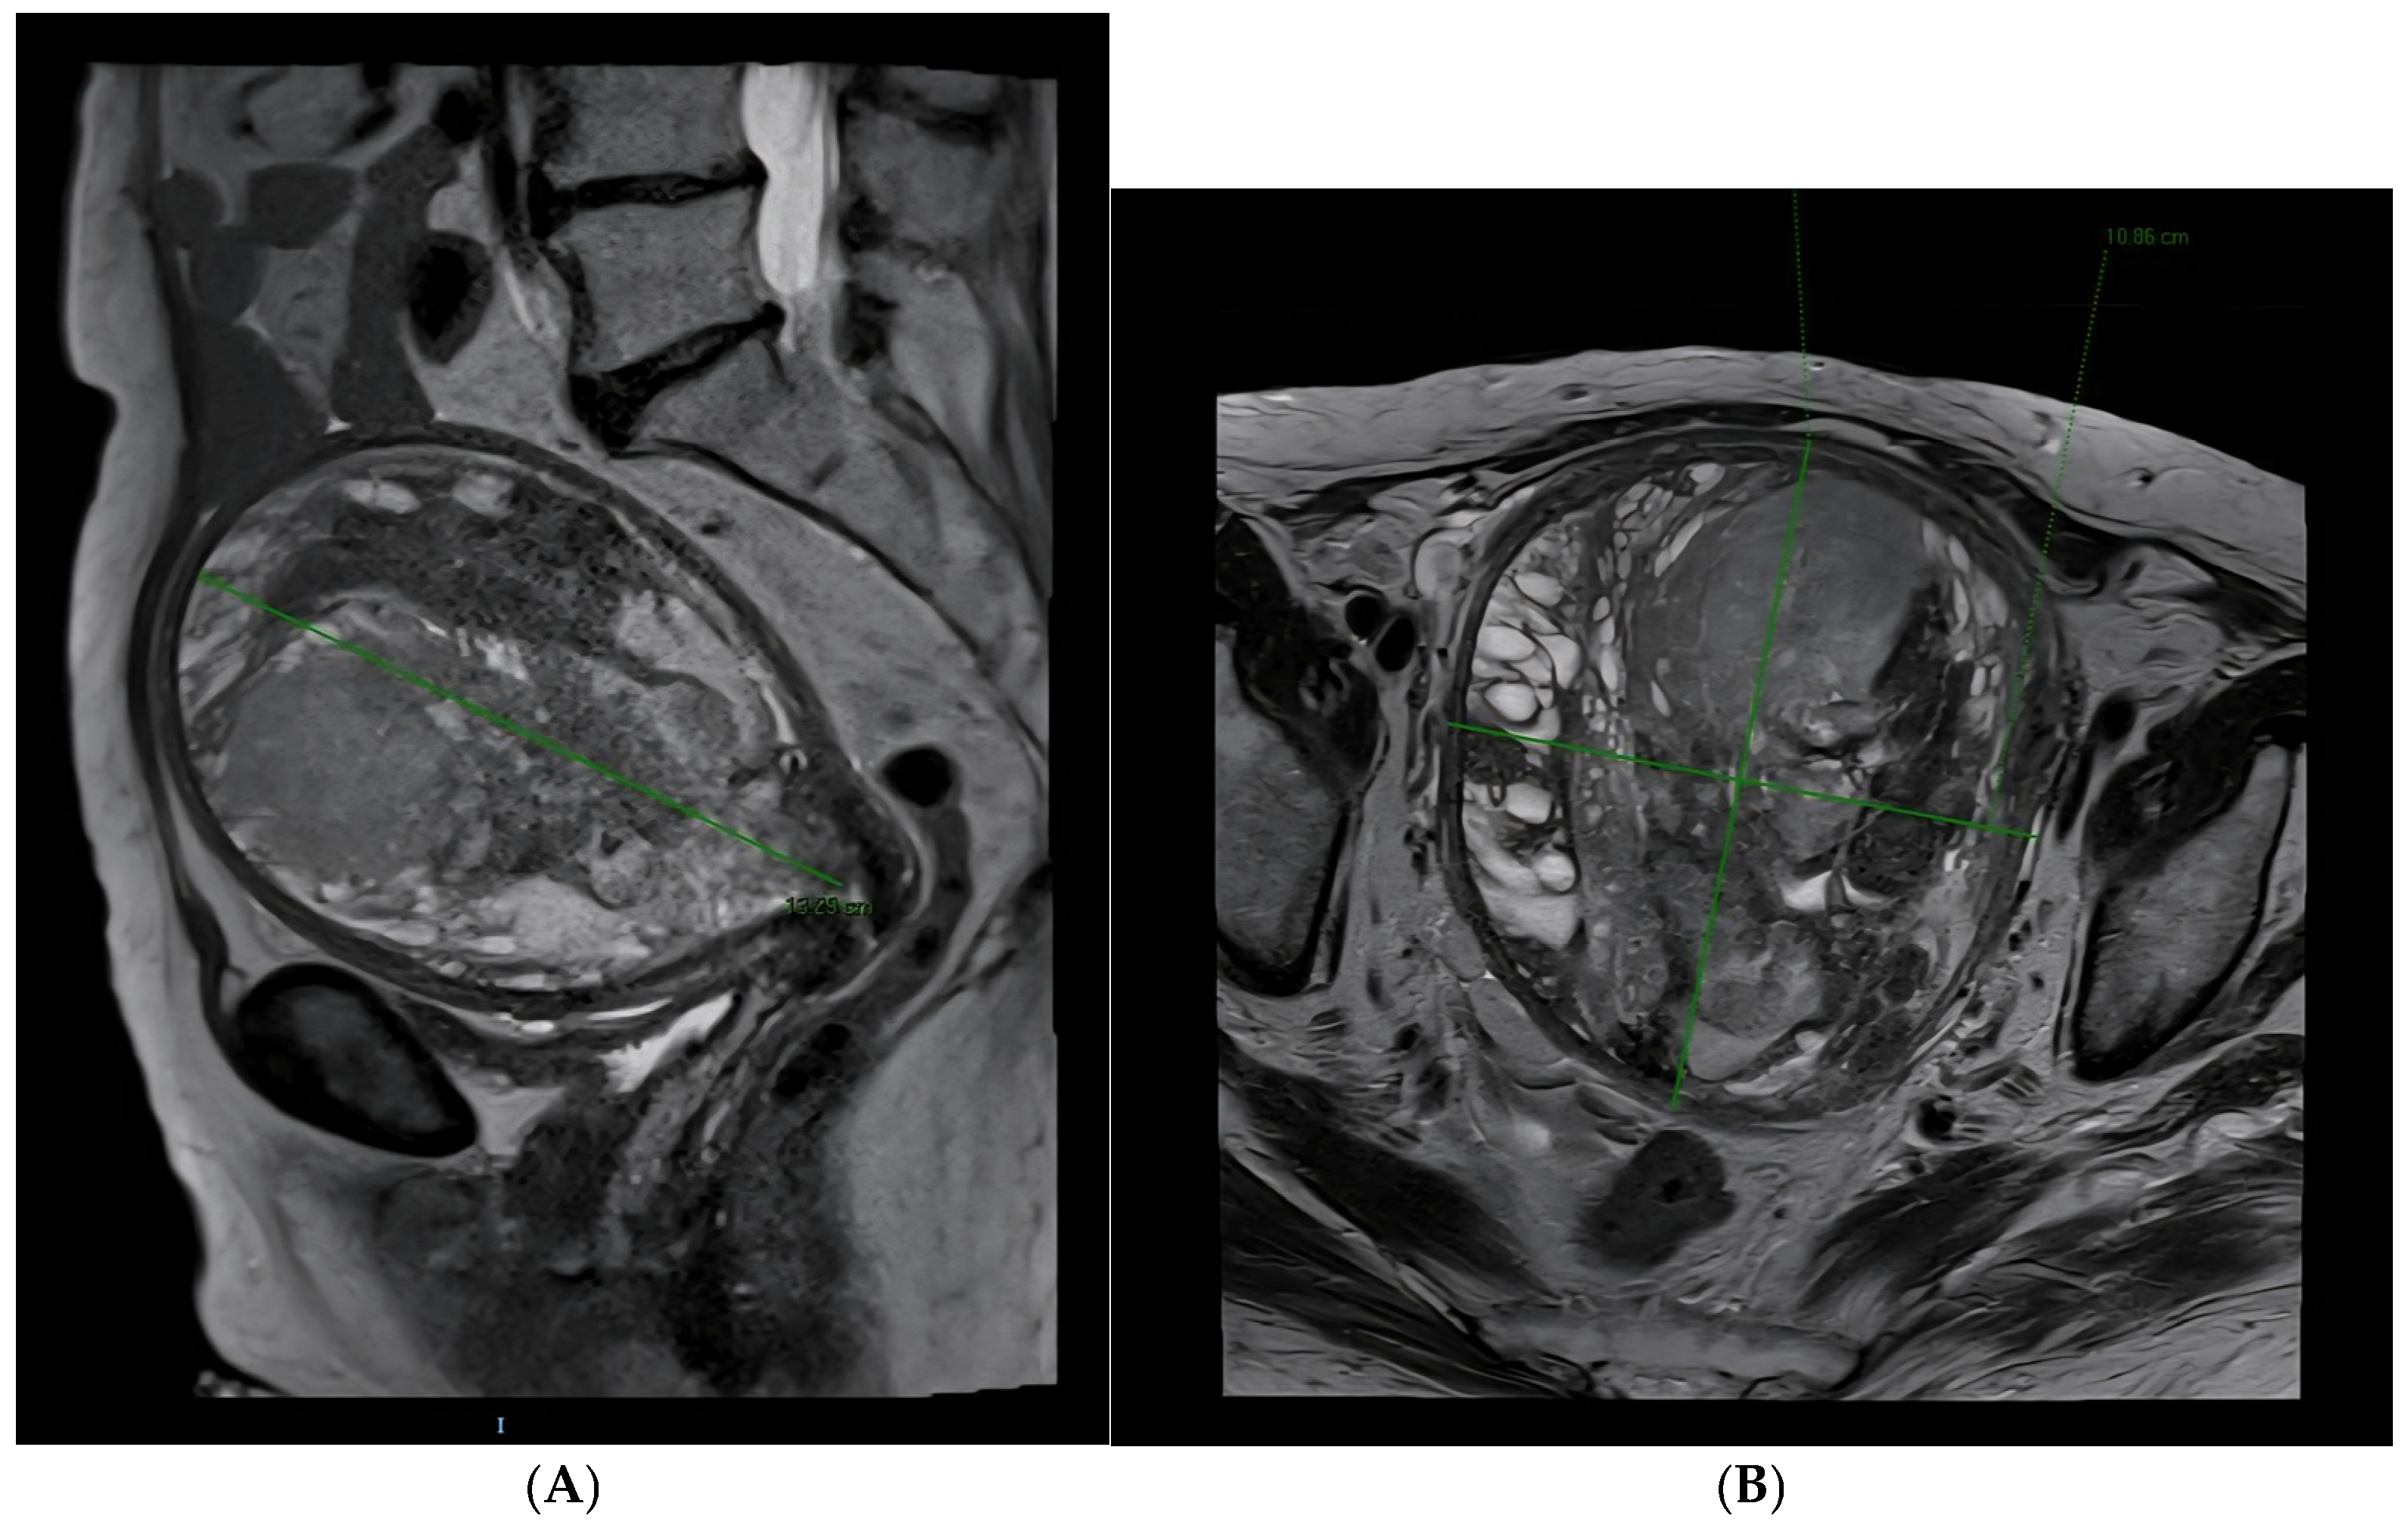

2. Case Presentation